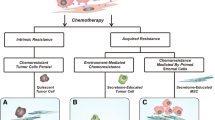

Similar to TAFs, MSCs also play a role in modulating cisplatin resistance. When treated with leptin, MSCs can upregulate TGF-β, leading to increased expression of autophagy-related genes such as ATG7, ATG5, and beclin1, ultimately inducing cisplatin resistance in osteosarcoma cells [128]. Additionally, MSCs in the tumor microenvironment of glioma can migrate to glioma cells through guidance from angiogenic cytokines. These migrated MSCs can enhance FOXS1 expression in glioma cells by secreting IL-6, triggering EMT and promoting resistance to temozolomide [129]. Downregulation of METTL3 in MSCs would lead to an increase in AKT protein levels which promoted MSCs adipogenesis, resulting in chemoresistance in acute myeloid leukemia cells [130]. MSCs can also interact with leukemia blasts, activating ABC transporters and facilitating the transition of acute myeloid leukemia cells into a more chemoresistant subset [131]. By secreting CXCL13, MSCs can upregulate the expression of BTK, NF-κB, BCL-2, and MDR-1 mRNA and protein, thereby enhancing the resistance of multiple myeloma cells to bortezomib [94]. The findings suggest that mesenchymal stem cells (MSCs) can play a role in promoting chemoresistance, including in endothelial cells. In glioblastoma, CCBE1, an extracellular matrix protein, stimulated hyper-angiogenesis and partial endothelial-to-mesenchymal transition in human microvascular ECs via the VEGFC/RHO pathway, conferring temozolomide resistance to cancer cells. Mechanistically, SP1 upregulated CCBE1 expression in temozolomide-resistant cells. CCBE1, aided by CAVIN1, was then secreted into the TME, promoting VEGFC maturation through the VEGFR2/VEGFR3/RHO pathway in vascular ECs, thus enhancing abnormal angiogenesis in temozolomide-resistant tumors [132]. The transformation of endothelial cells into mesenchymal stem cell-like cells was also observed in another study on glioblastoma, where the C-MET/WNT/β-catenin/MRP1 pathway was implicated in inducing temozolomide resistance [133]. Two separate studies reported an increase in angiogenesis in chemoresistant tumor tissue. Bone marrow-derived mesenchymal stem cells (BMSCs) were found to induce bortezomib resistance through the generation of HAPLN1 and MMP2, which activated NF-κB signaling [97]. Disrupting gap junctions between acute myeloid leukemia cells and BMSCs using carbenoxolone was shown to impair energy metabolism in tumor cells and reduce chemotherapy resistance [134]. The complex regulatory pathways through which non-immune stromal cells impact chemotherapy resistance present challenges for clinical experimentation. Moreover, the lack of classification of these cell subtypes in the studies mentioned detracts from their overall value. Specific mechanisms are detailed in Fig. 3, while Table 3 provides key references on chemoresistance.

Chemotherapy-induced hypoxia, vascular damage, and chronic inflammation are associated with the development of chemoresistance. Various infiltration cells in the TME play crucial roles in contributing to chemoresistance. Various factors promoted the formation of chemoresistance microenvironment, such as STAT3 pathway activation, EMT activation, and TAFs secreted pro-tumor exosomes. MDSCs: myeloid-derived suppressor cell; Tregs: regulatory T cells; MSCs: mesenchymal stem cells; BMSCs: bone marrow stromal cells; TAFs: Tumor-associated fibroblasts.; TAM: Tumor-associated macrophage